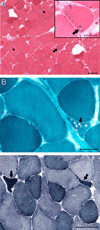

Limb-girdle muscular dystrophy primarily affects the muscles of the hips and shoulders (the "limb-girdle" muscles), although it is a heterogeneous disorder that can present with varying symptoms. There is currently no cure. We sought to identify the genetic basis of limb-girdle muscular dystrophy type 1 in an American family of Northern European descent using exome sequencing. Exome sequencing was performed on DNA samples from two affected siblings and one unaffected sibling and resulted in the identification of eleven candidate mutations that co-segregated with the disease. Notably, this list included a previously reported mutation in DNAJB6, p.Phe89Ile, which was recently identified as a cause of limb-girdle muscular dystrophy type 1D. Additional family members were Sanger sequenced and the mutation in DNAJB6 was only found in affected individuals. Subsequent haplotype analysis indicated that this DNAJB6 p.Phe89Ile mutation likely arose independently of the previously reported mutation. Since other published mutations are located close by in the G/F domain of DNAJB6, this suggests that the area may represent a mutational hotspot. Exome sequencing provided an unbiased and effective method for identifying the genetic etiology of limb-girdle muscular dystrophy type 1 in a previously genetically uncharacterized family. This work further confirms the causative role of DNAJB6 mutations in limb-girdle muscular dystrophy type 1D.